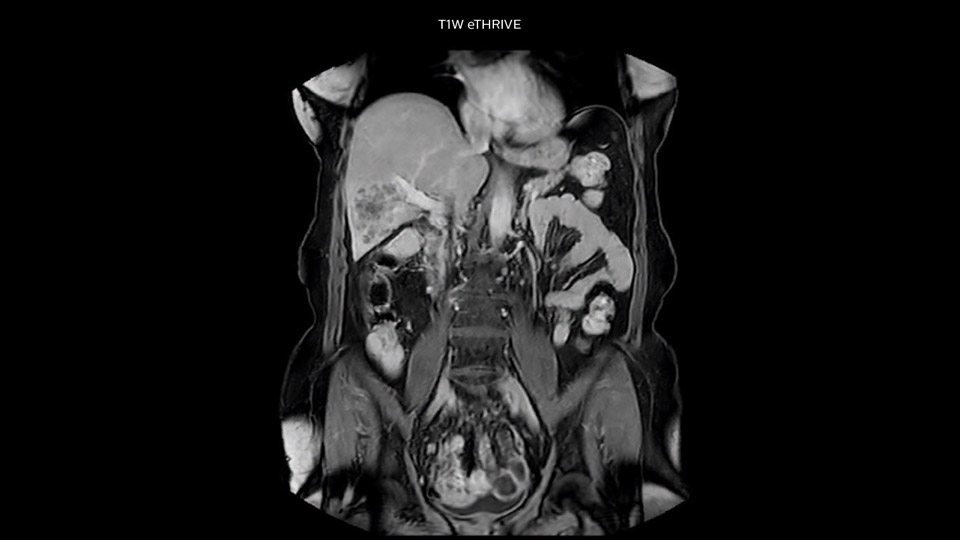

“Our liver exams are quite fast,” says Dr. Baumann. “If the patient tolerates it, we use an arms-up position to reduce the FOV and speed up the exam with dS SENSE.” “We acquire one transversal high resolution T2-weighted sequence with 3 mm slice thickness, for example for pancreas or liver lesions. Then we also add a T2 fat suppressed MultiVane XD SPIR sequence. We perform these two routinely in our liver imaging. We use high dS SENSE factors to significantly shorten scan times to 2-4 minutes, which can improve our protocol; it’s a very robust scan.” “We include mDIXON for the dynamic sequences because of the robust and homogeneous fat suppression we get with that. We had been using eTHRIVE, but we are now quite happy with mDIXON. Sometimes we use a medication to calm the bowels, to further improve the image quality.”

“We are more confident in our diagnosis if we don’t have to rescan the patient and compare it to other studies; this liver exam gives us good image quality in a faster time than the default system’s approach with arms down. That makes a difference for the patients, too. The shorter scan times, especially with the high dS SENSE factors, shorten the duration of the total examination. At the same time it’s more comfortable for the patient, to rest normally without holding the breath, just relaxing.”